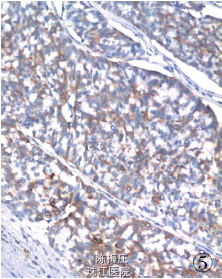

最后诊断:右乳神经内分泌癌;结肠腺癌;左侧卵巢Brenner 瘤。

遂行右乳肿物切除术+ 乙状结肠癌切除术及左侧附件切除术。术中所见:右乳肿物分叶状,与周围界清;乙状结肠肿物与周围无粘连;左侧卵巢肿物包膜完整,未见腹水。术后病理显示右乳腺内分泌癌,乙状结肠腺癌,左侧卵巢Brenner 瘤。